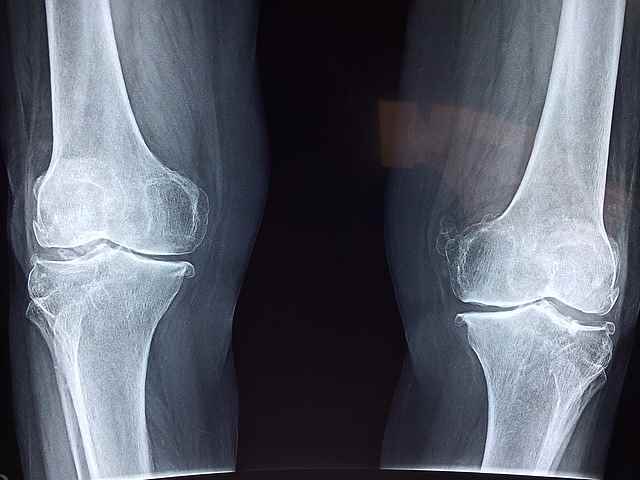

10. 관절통

관절 통증과 경직은 아마도 호르몬 변화와 에스트로겐 수치의 감소로 인한 갱년기 여성들 사이의 흔한 불만입니다. 요가, 태극권 또는 수영과 같은 유연성과 힘을 증진시키는 활동을 포함한 규칙적인 운동은 관절의 불편함을 완화하고 이동성을 개선하는 데 도움이 될 수 있습니다. 또한 건강한 체중을 유지하고 지방이 많은 생선, 견과류, 씨앗 및 다채로운 과일과 야채와 같은 항염증 식품을 식단에 포함시키면 관절 통증과 염증을 줄이는 데 도움이 될 수 있습니다.